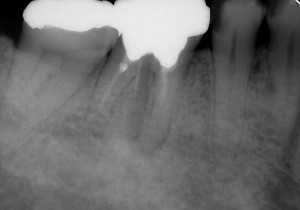

初診時は、時々歯肉から膿が出てきたり、鈍痛を感じることがあったとのこと。レントゲン写真を見ると確かに病気が出来ている影が・・・。さらに、この影の形を見るともしかしたら歯の根が割れているかもしれない。そうなると抜歯に移行しなければなくなる可能性もあることなど病気が治る喜びだけでなく、リスクや起こりうる可能性についても細かく説明させていただいた後に治療を開始しました。

↑初診時